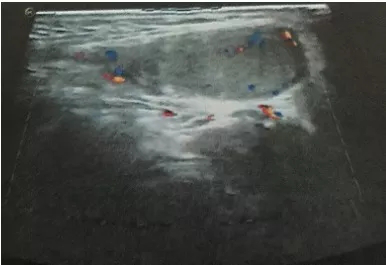

泌尿外科收治一名18歲男性青少年,反復(fù)右側(cè)睪丸疼痛2天,2天前出現(xiàn)右側(cè)睪丸疼痛稍腫脹,無(wú)其他不適,查陰囊彩超:右側(cè)睪丸、附睪較左側(cè)明顯增大,右側(cè)附睪頭實(shí)質(zhì)回聲增強(qiáng)不均,雙側(cè)睪丸、附睪血流信號(hào)未見(jiàn)明顯異常,當(dāng)時(shí)予對(duì)癥處理后疼痛好轉(zhuǎn)后回家。

近日,患者疼痛腫脹加重,再次至我院急診,行急診陰囊彩超:右側(cè)睪丸腫大回聲異常并其上方異?;芈晠^(qū),未見(jiàn)明顯血流信號(hào),未排睪丸扭曲可能,左側(cè)睪丸、附睪位置偏高,血流分布尚正常。

彩色多普勒超聲血流圖是最具有診斷價(jià)值的影像學(xué)檢查,可以詳細(xì)、實(shí)時(shí)地觀察睪丸內(nèi)的血流情況及其變化,目前被廣泛應(yīng)用于睪丸扭轉(zhuǎn)的診斷和鑒別診斷。睪丸內(nèi)動(dòng)脈血流信號(hào)明顯減少或消失是診斷本病的最可靠標(biāo)準(zhǔn)。